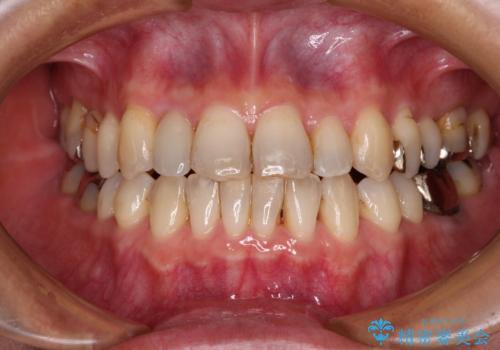

急速拡大装置 前歯の反対咬合をインビザラインで改善

- 前歯の反対咬合を気にして来院された患者様です。

上顎骨の幅が下顎骨よりも小さいので、拡大装置により骨幅を広げて上下関係を改善すると同時にワイヤー矯正で反対咬合の改善を図り、その後インビザラインにて歯並びを整えることとしました。

上顎前歯の矮小歯は矯正治療の途中でオールセラミッククラウンを装着し、左右のバランスを整えることとしました。

急速拡大装置の使用により奥歯の咬み合わせが劇的に変わり、その変化を利用して反対咬合を改善することができました。

治療期間中は奥歯が咬み合わず、食事が取りにくいなどの不都合がありましたが、最終的にはきれいに整えることができました。